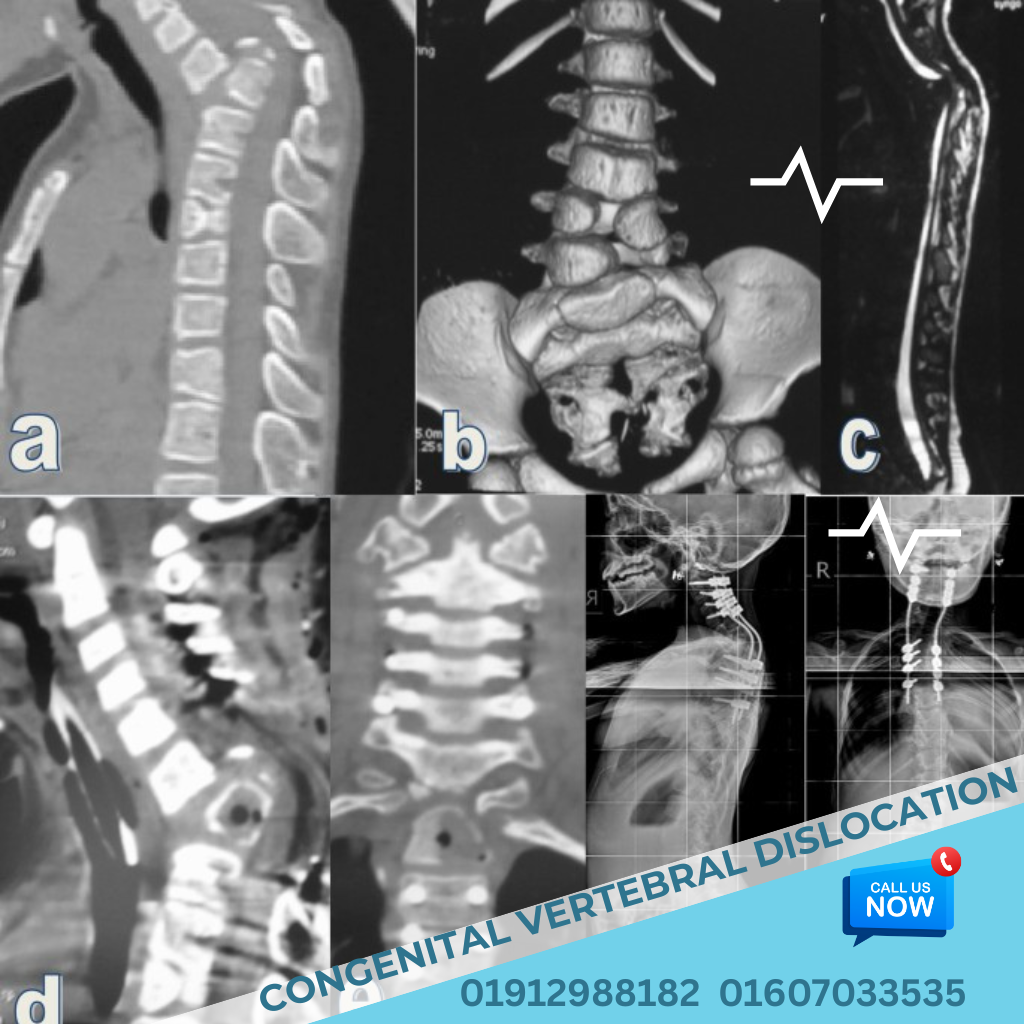

Congenital malformations of the spine comprise a large and diverse set of anomalies. Each part of the developmental process can give rise to a variety of pathologic states, and each state can present with a different clinical picture. Congenital and developmental spine disorders refer to abnormalities of the spine and spinal cord that are present at birth or develop in early childhood due to defective formation or closure of the neural tube during fetal life. These conditions are often rare and may affect the vertebral column, spinal cord, nerve roots, and surrounding soft tissue structures, causing significant neurological and orthopedic complications if not treated timely. In Bangladesh, such disorders are often diagnosed late, misinterpreted as orthopedic problems, or left untreated due to lack of pediatric neurosurgical expertise outside major medical centers. Dr. Md. Nafaur Rahman, one of Bangladeshβs top pediatric neurosurgeons, specializes in the diagnosis and surgical treatment of rare congenital and developmental spine anomalies, offering comprehensive care for children across the country. π Challenges in the Bangladeshi Context πΆ Birth defects often go unnoticed due to limited antenatal care and lack of fetal anomaly scans πΈ Parents may dismiss early symptoms like foot deformity or urinary issues π₯ Children are often referred late to pediatric neurosurgeons after irreversible neurological damage β Limited centers in Bangladesh offer MRI-based evaluation and surgical correction of spinal malformations π§ Many children live with treatable conditions that lead to progressive disability without proper care π¨ββοΈ Why Choose Dr. Md. Nafaur Rahman? π Specialized in pediatric spinal neurosurgery and neural tube defects π₯ Operates at NINS, Bangladeshβs national-level neuroscience hospital πΆ Founder of Bangladesh Paediatric Neurocare Centre β A one-stop solution π§ Offers minimally invasive surgery where possible π§ Deep commitment to child-focused, family-friendly care π Early Diagnosis Saves Futures β Act Now Dr. Md. Nafaur Rahman Assistant Professor, Pediatric Neurosurgery, NINS Chief Consultant, Bangladesh Paediatric Neurocare Centre π± For Serial/Appointments: π 01912988182 | π 01607033535 π Visit: www.neurosurgeonnafaur.com